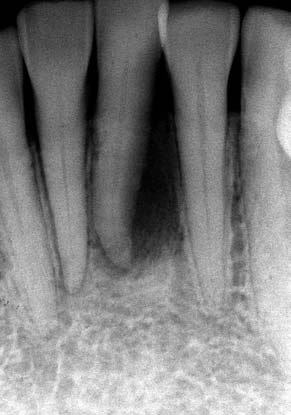

(図1)初診時(1975年10月15日)、38歳。歯肉出血が主訴で紹介された。当時、歯周疾患治治療は一部の臨床家以外はあまり関心が払われていなかった

(図2)初診時(1975年10月15日)、38歳。まず徹底的なPlaque Controlから始めた